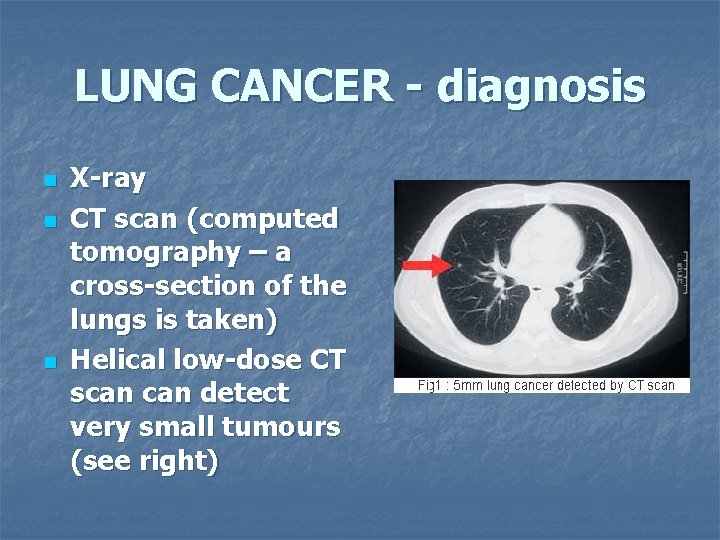

LUNG CANCER - diagnosis n n n X-ray CT scan (computed tomography – a cross-section of the lungs is taken) Helical low-dose CT scan detect very small tumours (see right)